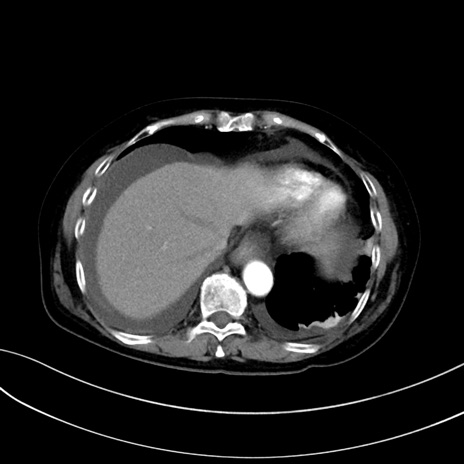

症例13 CT(横断像)1日半後